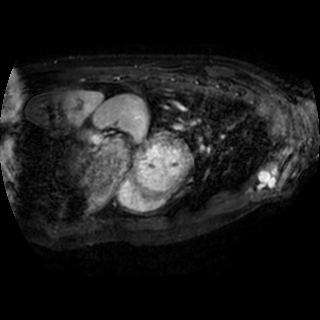

The integration of deep learning systems into healthcare has been hindered by the resource-intensive process of data annotation and the inability of these systems to generalize to different data distributions. Foundation models, which are models pre-trained on large datasets, have emerged as a solution to reduce reliance on annotated data and enhance model generalizability and robustness. DINOv2 is an open-source foundation model pre-trained with self-supervised learning on 142 million curated natural images that exhibits promising capabilities across various vision tasks. Nevertheless, a critical question remains unanswered regarding DINOv2's adaptability to radiological imaging, and whether its features are sufficiently general to benefit radiology image analysis. Therefore, this study comprehensively evaluates DINOv2 for radiology, conducting over 100 experiments across diverse modalities (X-ray, CT, and MRI). To measure the effectiveness and generalizability of DINOv2's feature representations, we analyze the model across medical image analysis tasks including disease classification and organ segmentation on both 2D and 3D images, and under different settings like kNN, few-shot learning, linear-probing, end-to-end fine-tuning, and parameter-efficient fine-tuning. Comparative analyses with established supervised, self-supervised, and weakly-supervised models reveal DINOv2's superior performance and cross-task generalizability. The findings contribute insights to potential avenues for optimizing pre-training strategies for medical imaging and enhancing the broader understanding of DINOv2's role in bridging the gap between natural and radiological image analysis. Our code is available at https://github.com/MohammedSB/DINOv2ForRadiology